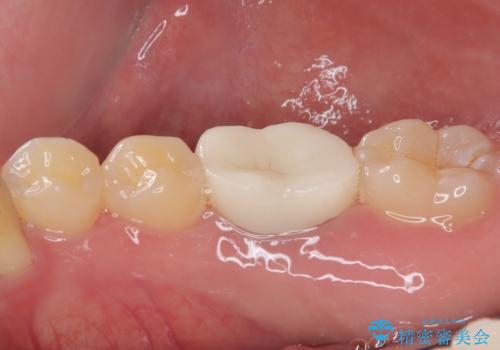

見た目、噛み合わせともに満足していただけました。

歯質と被せ物(クラウン)の境目も適合の良いものができました。